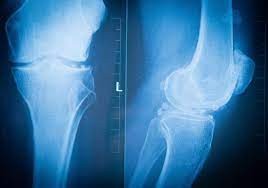

Bouger est l'enjeu essentiel pour tous les malades atteints d' arthrose du genou, ce pourquoi le laboratoire pharmaceutique Sanofi lance un nouveau programme « L'Arthrose en mouvement » et propose aux patients et aux médecins des outils pour une meilleure prise en charge de la gonarthrose (l'arthrose du genou).

La gonarthrose touche 3,5 millions de Français, soit 1 sur près 10 millions de Français atteints d' arthrose . Trop souvent considérée comme une simple usure liée au vieillissement, l'arthrose est une véritable maladie qui, si elle ne se guérit pas, se soigne. Cette maladie implique les trois tissus de l'articulation : le cartilage, l'os sous chondral (zone osseuse située sous le cartilage) et la membrane synoviale qui tapisse l'intérieur de l'articulation.